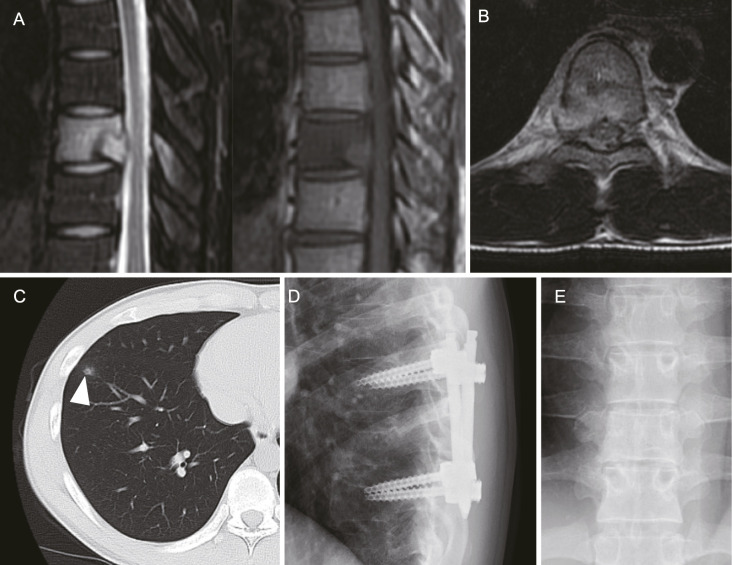

Results: Four male patients aged between 21 and 28, each with a single spinal LCH lesion (T6, T5, and C5) except one case (T5 and T7), were treated. Diagnoses were confirmed via biopsy (two open, two needle biopsies). Whole-body computed tomography or bone scintigraphy revealed no additional LCH lesions in any patient, except in one patient with a small lung nodule. All patients presented with severe back or neck pain and pathological fractures at the affected vertebra. Thoracic LCH cases received percutaneous pedicle screw fixation, while the cervical case was managed with conventional posterior instrumentation using lateral mass screws. After surgery, all patients experienced significant pain relief, halted bone lysis, and rapid new bone formation. One patient underwent chemotherapy postsurgery. Over 3 years of follow-up, imaging studies revealed no recurrences of the disease.

Conclusions: Posterior instrumentation, without the need for curettage or bone grafting, is a promising surgical treatment for adult spinal LCH. This method may effectively halt lesion progression, prevent spinal deformity, and avert neurological deficits in the patients with progressive spine lesion where conservative treatment may not adequately prevent vertebral fractures.